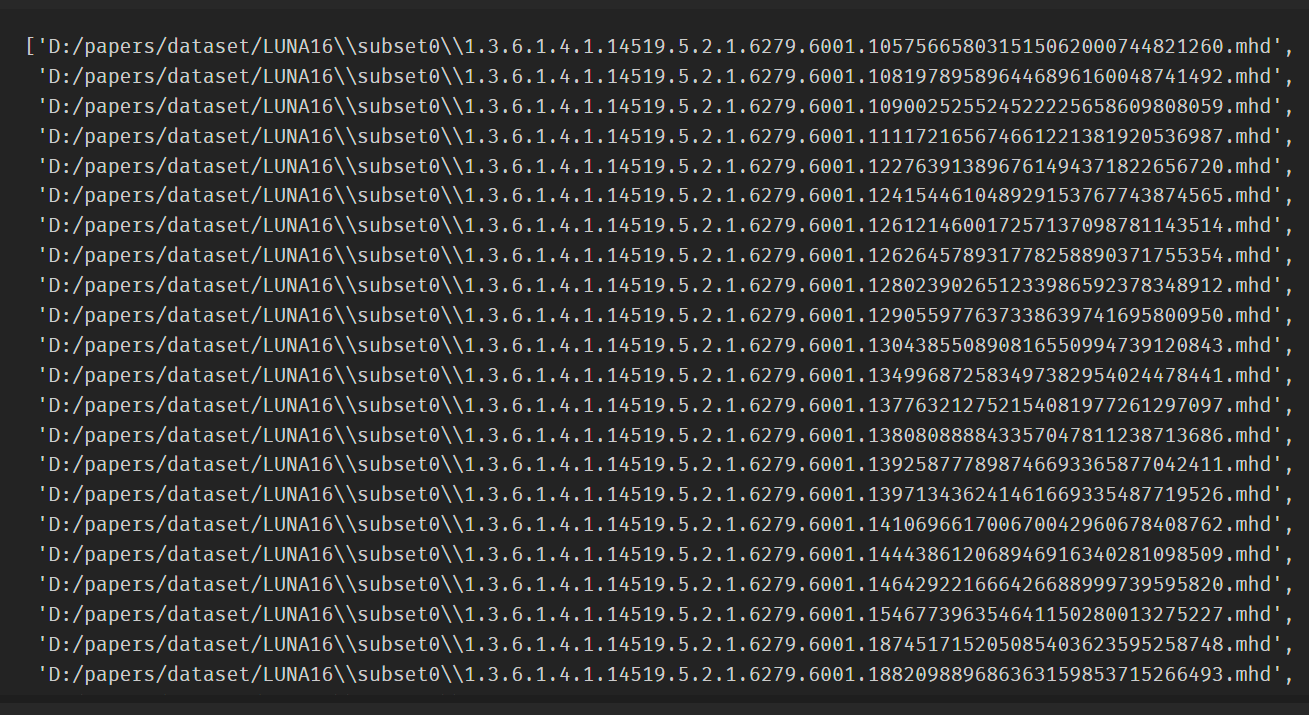

导入subset0和subset1的.mhd

我们的CT数据来⾃2个⽂件:⼀个.mhd⽂件包含元数据头信息,另⼀个.raw⽂件包含组成三维数组的原始数据。

LUNA16中有 subset0-subset4 约35G的CT扫描影像数据(完整的数据集包含subset0~9约200多G的数据),本文仅选取了subset0和subset1;

我们所讨论的CT扫描的每个⽂件的名称都以⼀个称为系列UID的唯⼀标识符开始,该名称依据医学中的数字成像和通信(DICOM)命名法。例如,对于uid1.2.3系列,有2个⽂件——1.2.3.mhd和1.2.3.raw

mhd_list = glob.glob(path+'subset*/*.mhd')

功能解析:

glob.glob 接受一个字符串参数,该参数可以包含通配符字符(例如 * 和 ?)以及路径分隔符,然后它会在指定的路径中搜索与模式匹配的文件路径,并将匹配的文件路径返回为一个列表。